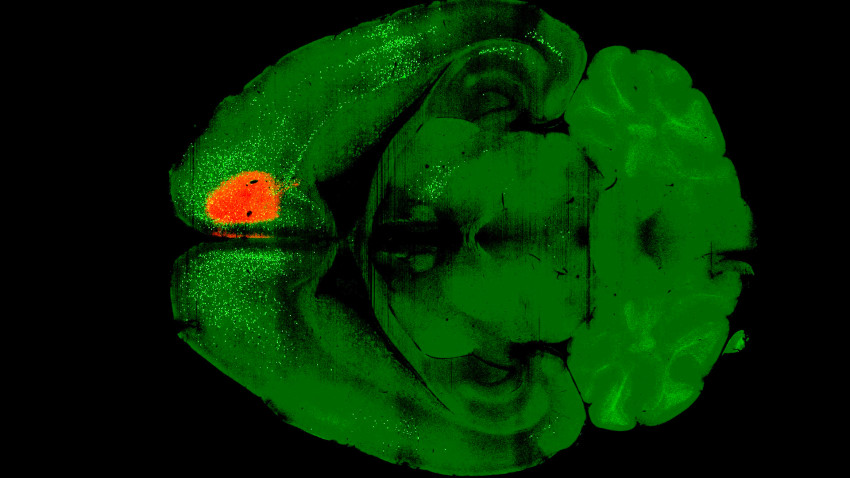

The researchers first administered a dose of psilocybin to the frontal cortical pyramidal neurons of mice. One day later, they introduced the modified rabies virus, which labels connected neurons with fluorescent proteins. After a week, they imaged the brains of the mice and compared them to control subjects that received only the virus. This process revealed that psilocybin significantly weakened recurrent cortical connections, shedding light on why individuals with depression tend to fixate on negative thoughts.

The researchers also discovered that psilocybin enhances the connections between sensory areas of the brain and subcortical regions, which are essential for turning sensory perceptions into actions. Kwan found this broader impact surprising, as he initially anticipated that the rewiring would be confined to a limited number of brain regions.